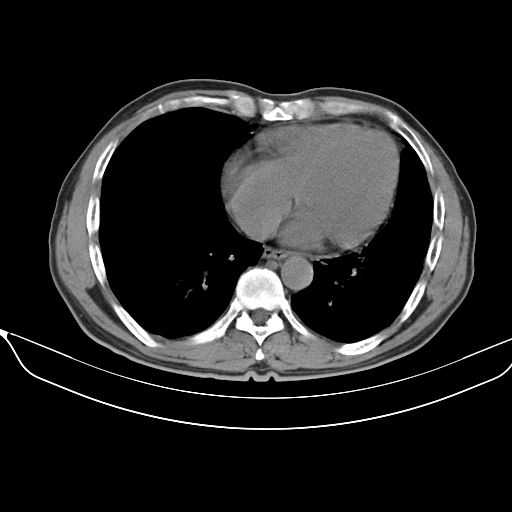

以下是引用shuiyuan在2010-3-1 10:45:00的发言:[br]考虑左肺上叶中心型肺癌伴阻塞型炎症,邻近胸膜受侵。

以下是引用心路寻觅在2010-3-1 10:23:00的发言:[br]1、考虑左肺上叶周围型肺癌[br]2、右上肺陈旧性病灶。[br][br][本贴已被 心路寻觅 于 2010-3-1 10:40:18 修改过]